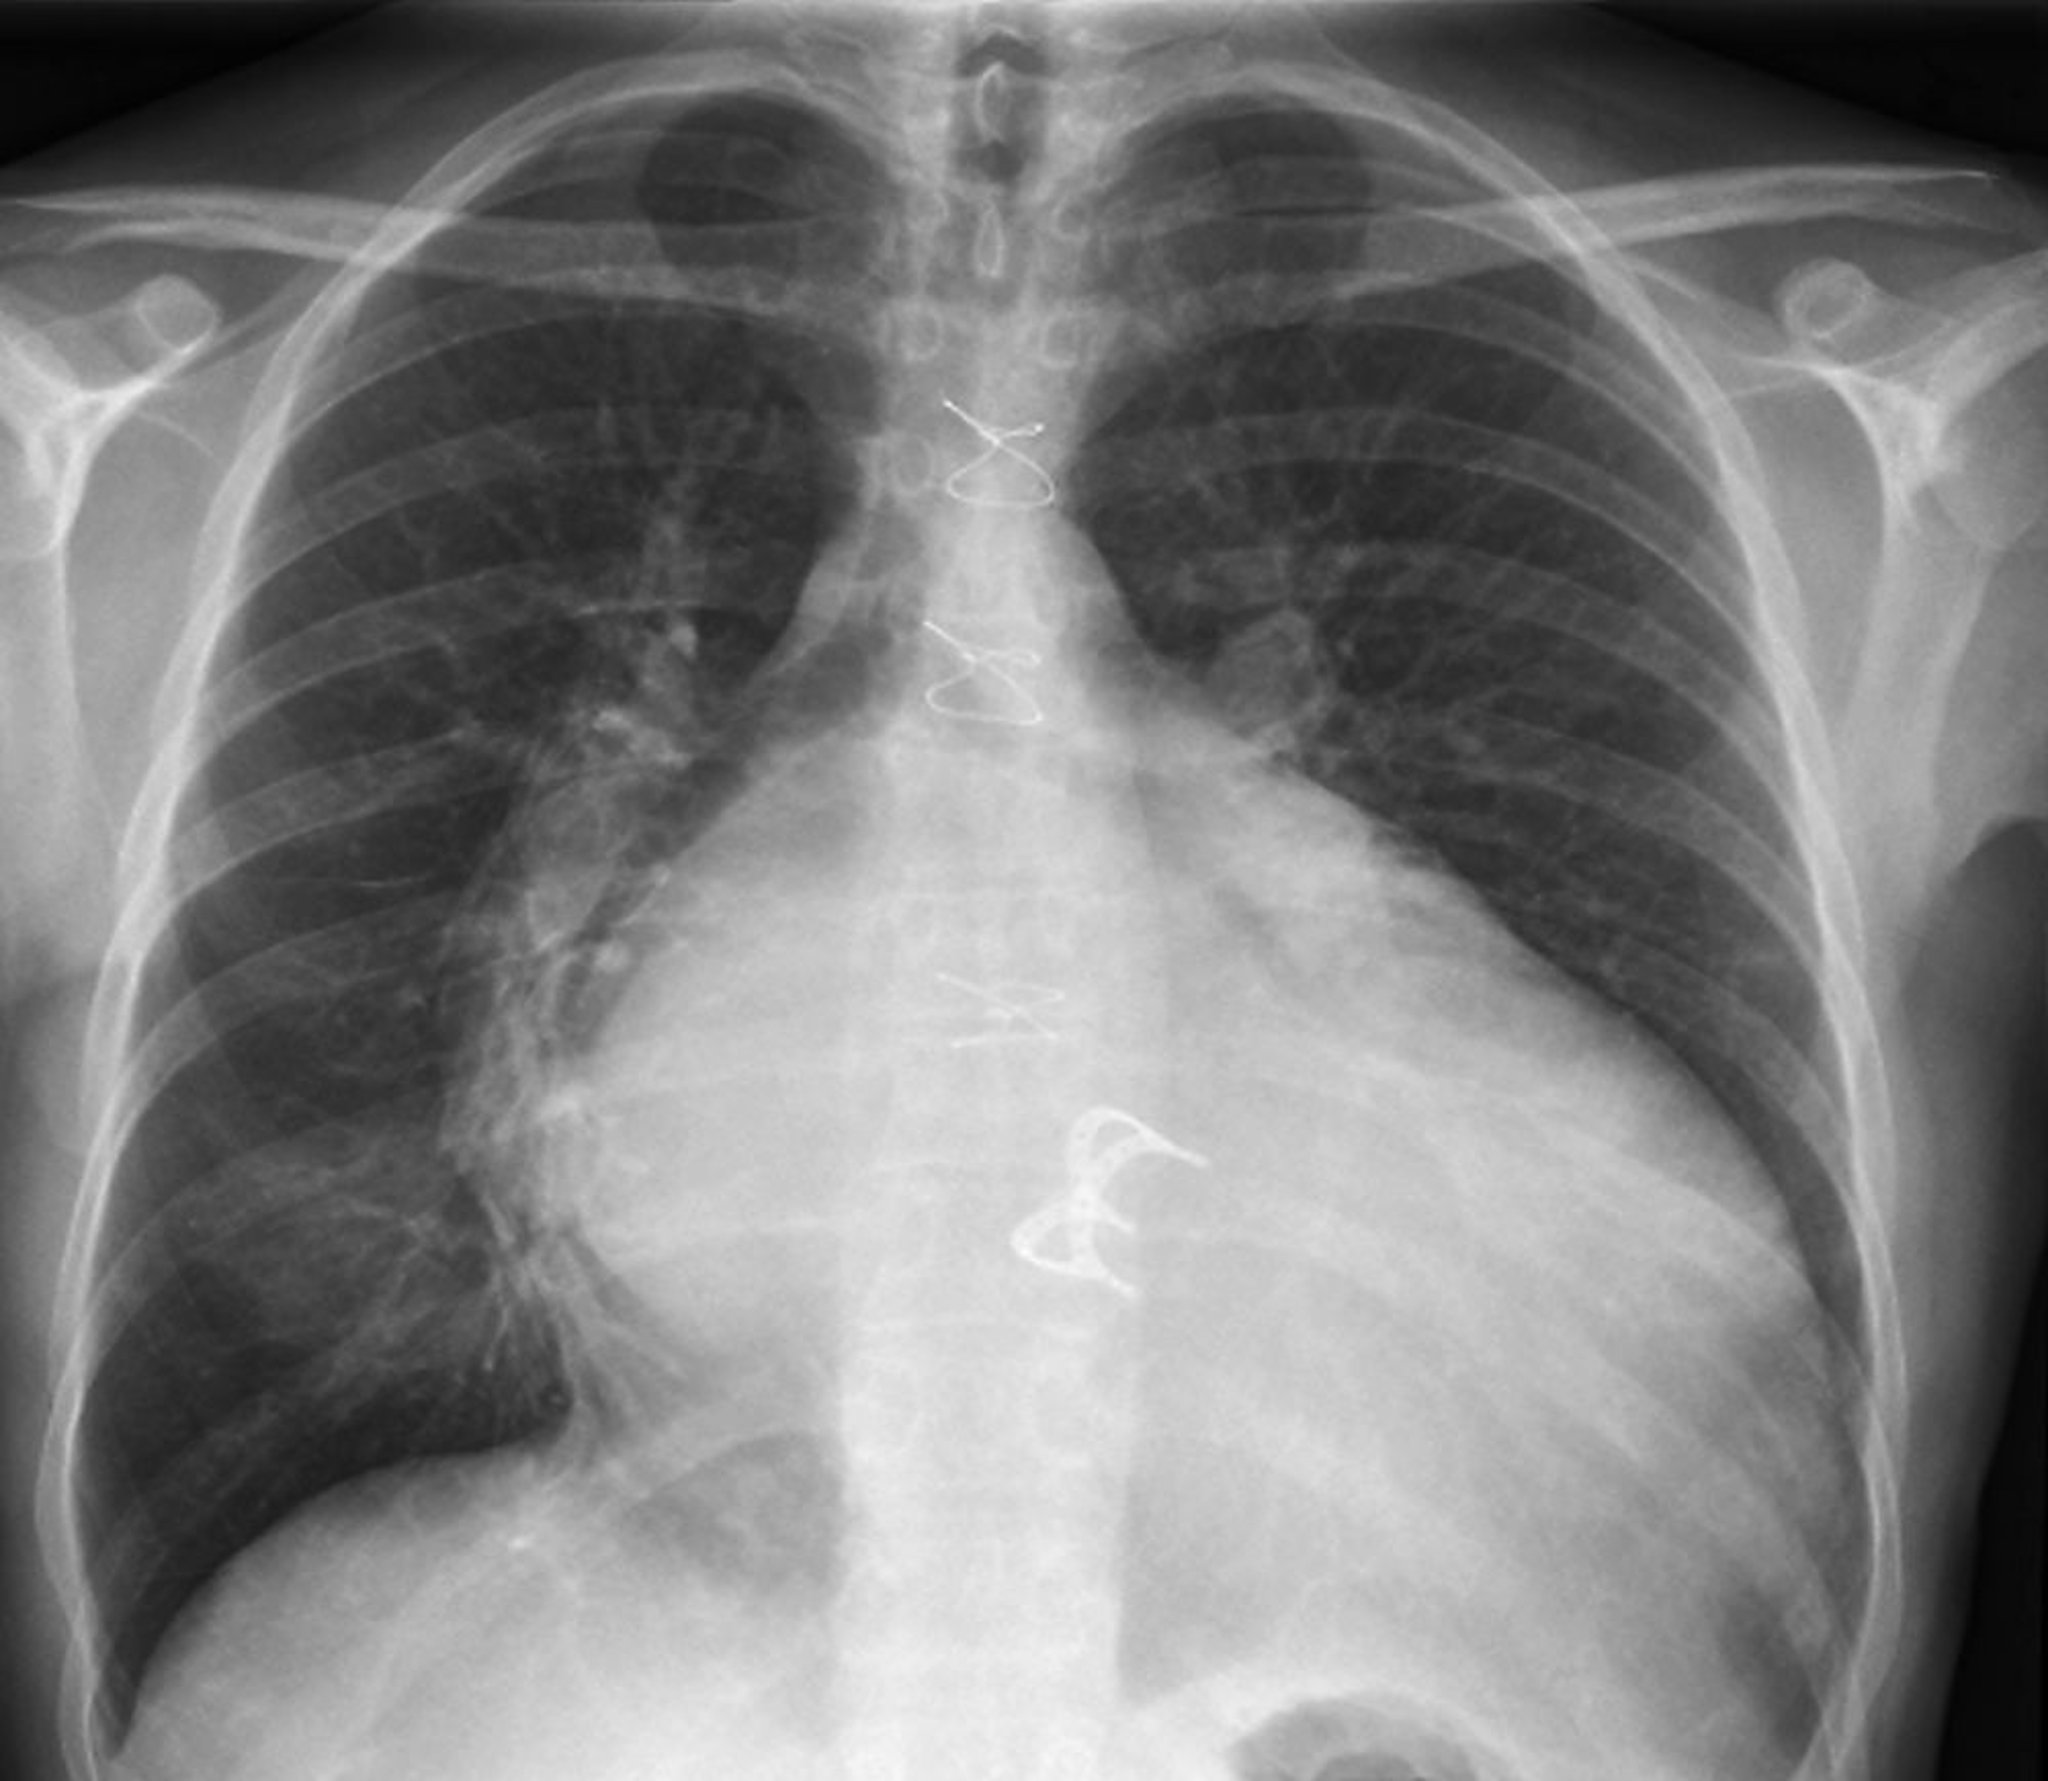

Рентген грудной клетки (искусственный клапан сердца)

На данном рентгеновском снимке показан искусственный клапан сердца в виде небольшой белой дуги внизу центральной части снимка. Швы, используемые для закрытия грудной клетки, показаны уходящими вниз в центре снимка. Признаки увеличения левого предсердия включают видимую интенсивность тени левого предсердия в правой части грудной клетки (синяя стрелка, признак двойной плотности), увеличенное (> 7 см) расстояние между границей левого предсердия в правой половине грудной клетки и левого главного бронха, выпуклость по верхнему краю левого сердца, образованная увеличенным ушком левого предсердия (красная стрелка) и расширением киля трахеи с увеличением расстояния между левым и правым главными бронхами. Признаки увеличения левого желудочка включают расширение сердечного силуэта и смещение левого края сердца влево и вниз.